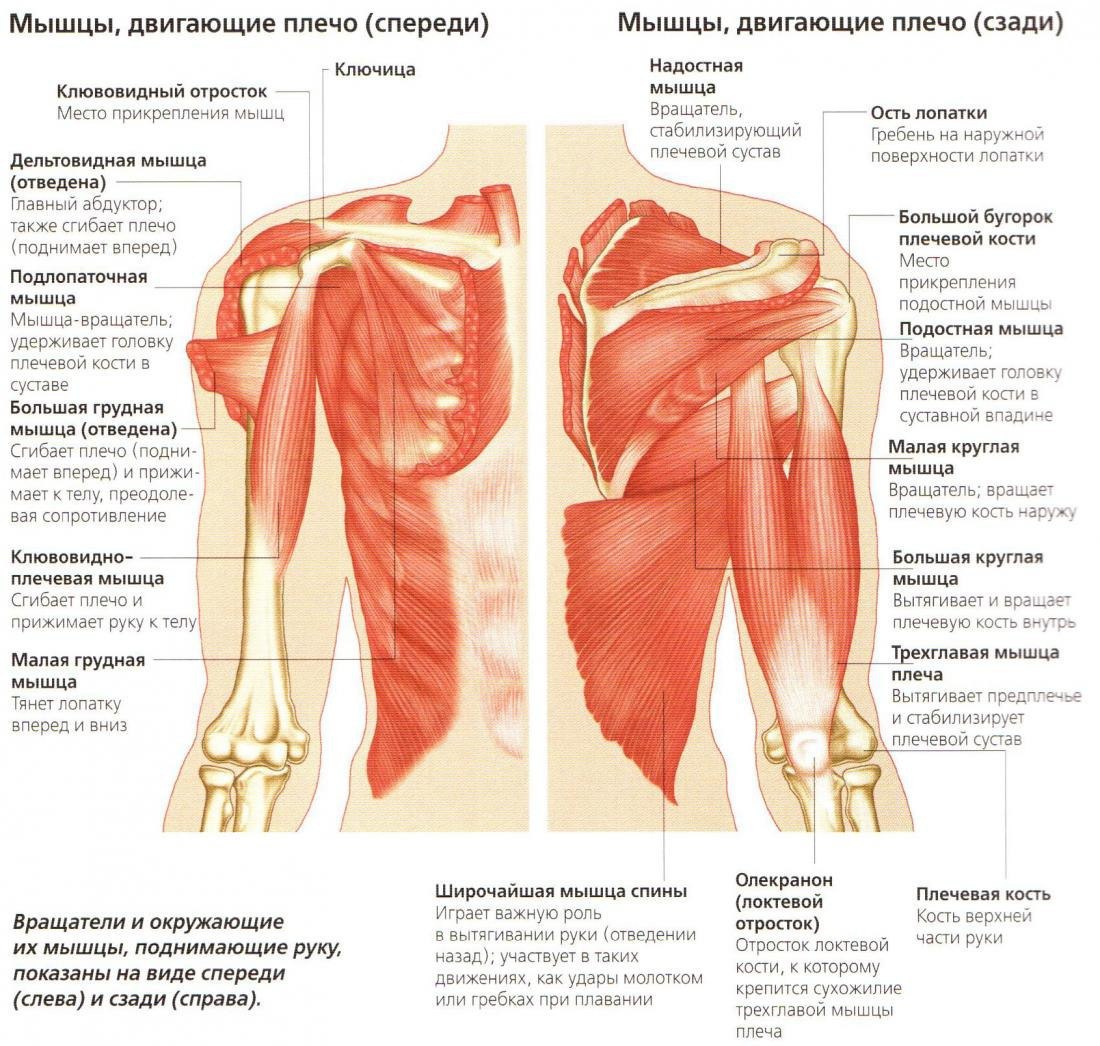

Фотографии поддельтовидной мышцы плечевого сустава